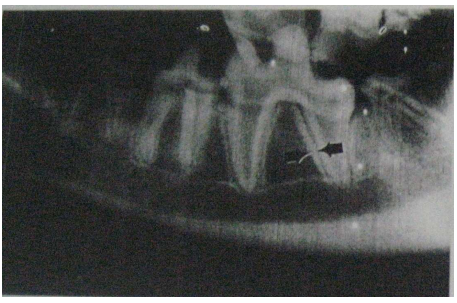

![]() |

| Hasil rontgen dari maxilla anjing umur 3 tahun |

Gambaran radiographi dari tulang mandibula dan maxilla sebaiknya menggunakan lima sudut pandang radiographi yaitu dorsoventral, lateral, right oblique, left oblique dan intra oral.

Kebutuhan lima sudut pandang ini disebabkan oleh adanya kesulitan untuk melakukan interperetasi akibat adanya berlapis-lapis tulang yang mengganggu interpretasi.

Sehingga mengetahui bentuk tulang secara normal sangat penting sekali untuk mengetahui perubahan yang terjadi. Bentuk kesimetrisan tulang merupakan salah faktor yang dapat dijadikan sebagai acuan adanya fraktur.